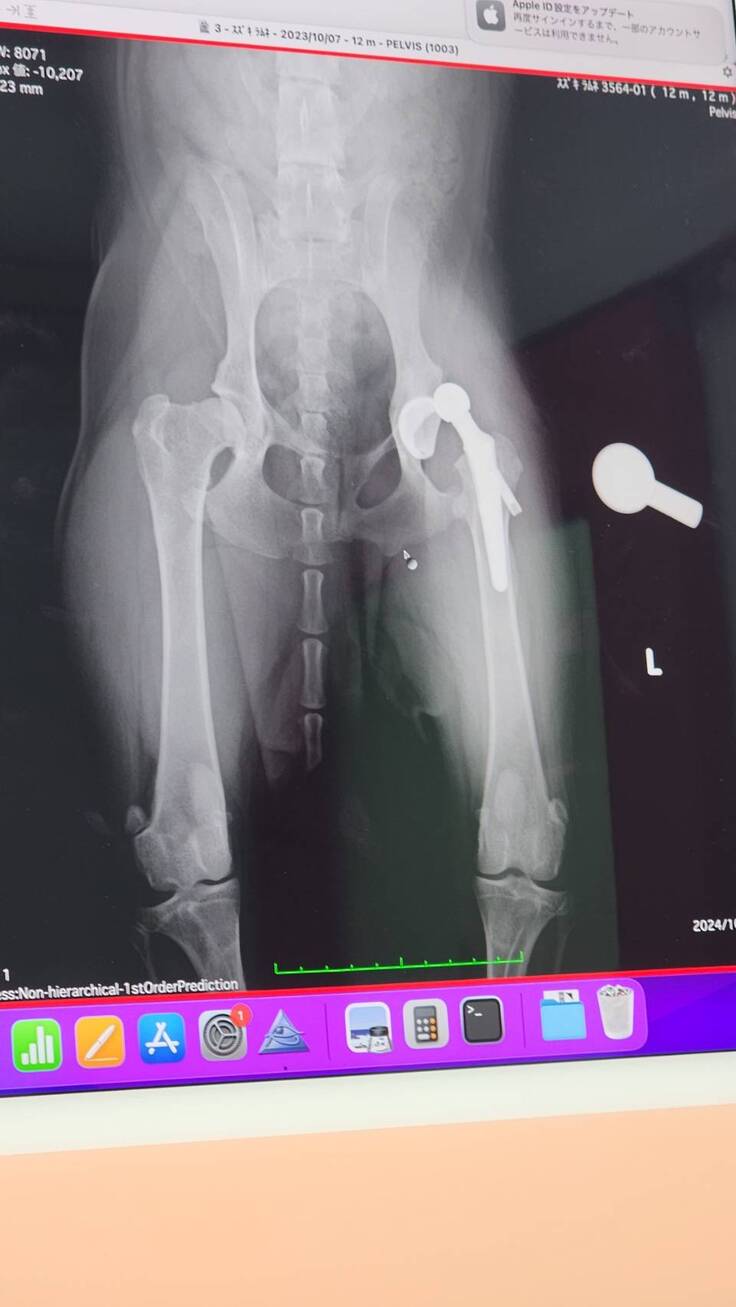

退院予定日の2日前に病院から連絡が入り、人工股関節が脱臼してしまっていると報告を貰いました。

緊急で昨日再手術があり本日10/13が退院予定日でしたが、病院で現状と今後の説明がありました。

もともと亜脱臼状態で生活していたため筋肉もそのように作られており人工股関節に違和感がありはずれてしまった。さらに人が好きすぎて看護師さんを見ただけでもはしゃいでおりそのタイミングで外れてしまった。いくつかの過程を聞き最後に。。。

1・再手術のためさらに2週間入院 退院予定早くて10月末